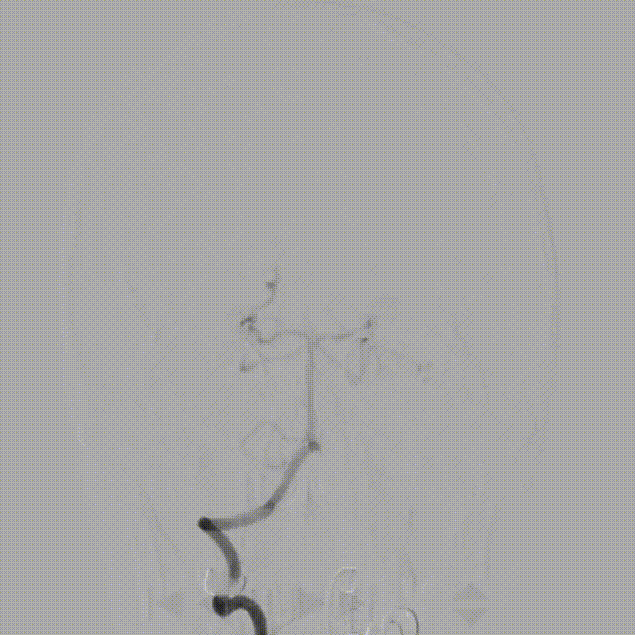

右侧颈内动脉造影动脉末期可见左侧大脑前动脉经软膜支向左侧大脑中动脉供血区域代偿,后循环未向左侧大脑中动脉代偿。

左侧颈总动脉造影可见颈内动脉闭塞,动脉末期可见颈外动脉经眼动脉向颈内动脉代偿,颈内动脉末端以远不显影。

在泥鳅导丝及5F MPA1造影管配合下将6F股动脉长鞘至于左侧颈总动脉行路图,在200cm Sur-reach®微导丝配合下将2.5*15mm颅内球囊扩张导管扩张后,将6F导管鞘通过颈内动脉起始部闭塞段,行路图可见颈内动脉颈段至海绵窦段后膝处血栓影,左侧大脑中动脉闭塞。